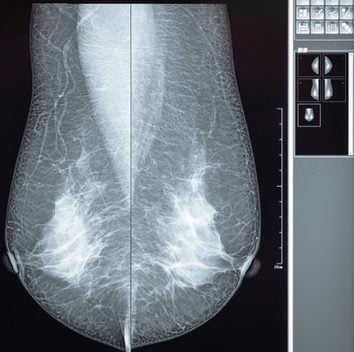

Comprehensive Review of Breast Imaging 2022

Comprehensive Review of Breast Imaging 2022 online CME program begins with an overview of breast MRI, moves into state-of-the-art coverage of breast imaging, then wraps up with breast ultrasound. It offers a unique learning opportunity for diagnostic radiologists, breast imaging specialists, technologists, and other healthcare providers interested in breast radiology.